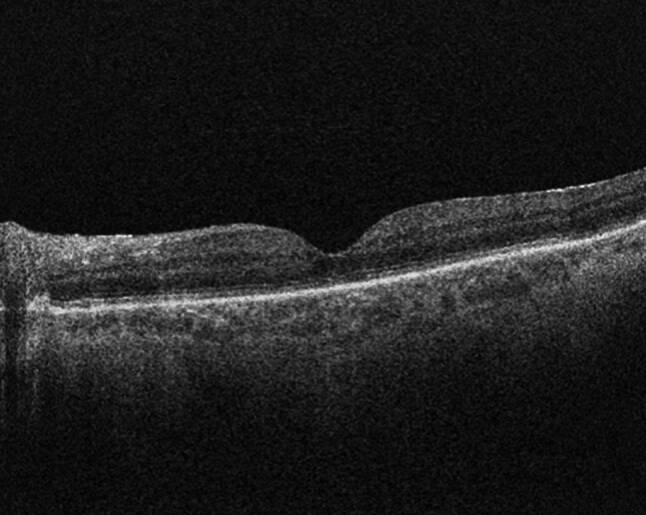

如果不及时治疗,视网膜脱离有可能成为永久性致盲疾病,因此是眼科紧急情况。这篇综述将概述历史,发病机制,临床表现,以及目前和未来的处理视网膜脱离。

Retinal detachments are ophthalmic emergencies given their potential to become a permanently blinding disorder if left untreated. This review will outline the history, pathogenesis, clinical presentation, and current and future management of retinal detachments.